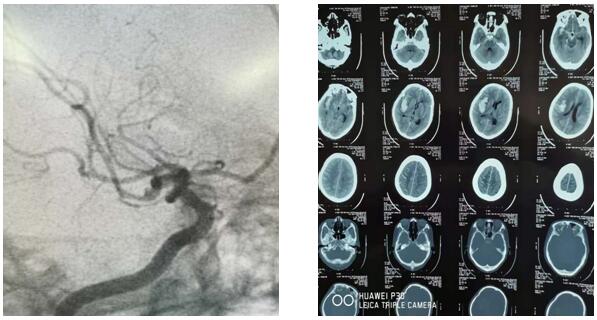

2019年6月7日10时30分,延安大学咸阳医院神经外科二病区收治了一颅脑动脉瘤破裂出血患者,入院时头颅CT示右侧颞叶脑出血,量约30ml,破入蛛网膜下腔,由于出血部位及形态与常见的高血压脑出血不同,主管医师王海波考虑动脉瘤出血可能性大,建议行脑血管造影检查,发现患者颅脑右侧大脑中动脉下干近端血泡样动脉瘤。瘤体大小为1mm*2mm,经科主任刘小雷、责任总医师游文良及全科医师讨论后,判定出血原因为“血泡样”动脉瘤破裂。手术组最终决定在显微镜下施行外科动脉瘤夹闭手术,同时清除血肿。由于“血泡样”动脉瘤术中发生破裂大出血可能性较大,手术风险也随之加大。相对血管内介入治疗,此类手术为高难度、高风险的手术。需要更加扎实的血管解剖、颅底解剖知识和娴熟的手术技巧。因此动脉瘤夹闭手术也被神经外科医师们誉为“刀尖上的舞蹈”。 而这次的舞蹈是在最容易破裂大出血的“血泡”上表演。